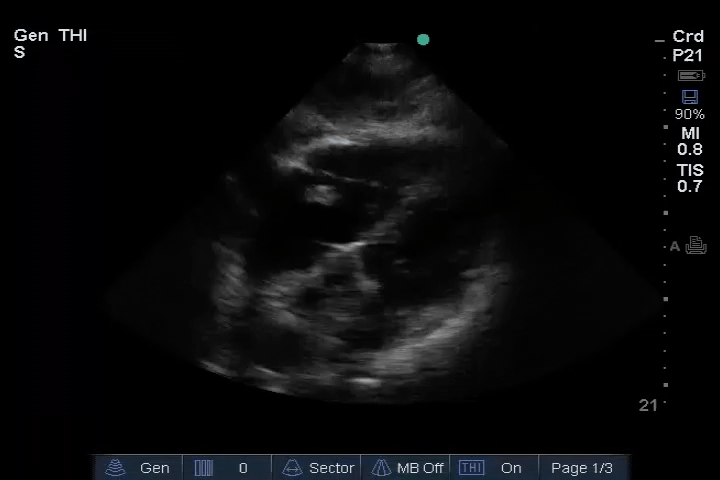

10_Heart_SC – Dilated RV, RA embolus

11_Heart_A4CH – Dilated RV, RA embolus